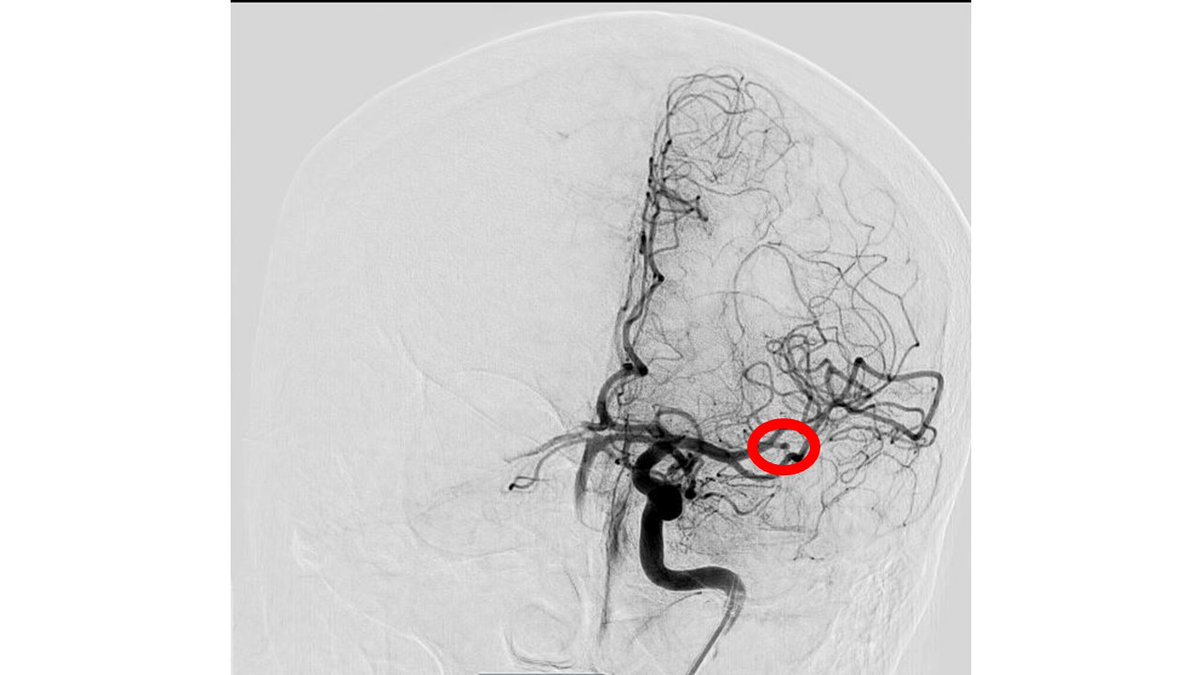

Thank you to Dr. Wei-Chiang, Chen out of #CMUH, #Taiwan🇹🇼, for sharing these great images from a first case using #RED43 in Left M2. Fantastic first pass and final TICI3 result. @PenNeuro